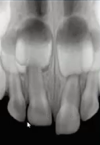

What type of injury is this?

Complete avulsion

What injuries are seen here

Extrusion and luxation, and crown fracture